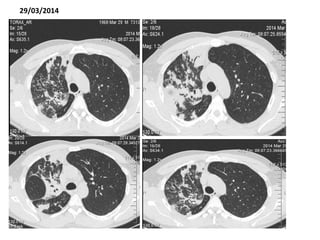

29/03/2014

INFECTOLOGIA

01/04/2014

«Paciente de 48 años de edad, TBC pulmonar con

antecedente de abandono de tratamiento, neumonía

atípica, en quien se reporta baciloscopia positiva, TAC de

al resolución muestra proceso granulomatoso activo

crónico. Paciente actualmente estable se recomienda

terapia tetraconjugada* ( se inicia el día de hoy) según las

guias de manejo nacional y culminar terapia antibiótica

biconjugada, piperazilina tazobactam y claritromicina, por

14 días»

*(isoniazida+rifampicina+ethambutol+pirazinamida)